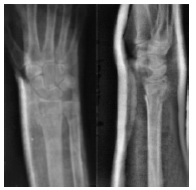

ճաճաևչոսկրի դիստալ Մետաէպիֆիզի տեղաշարժված կոտրվածք

Կոևտրոլ`դիաֆիքսացիայից հետո